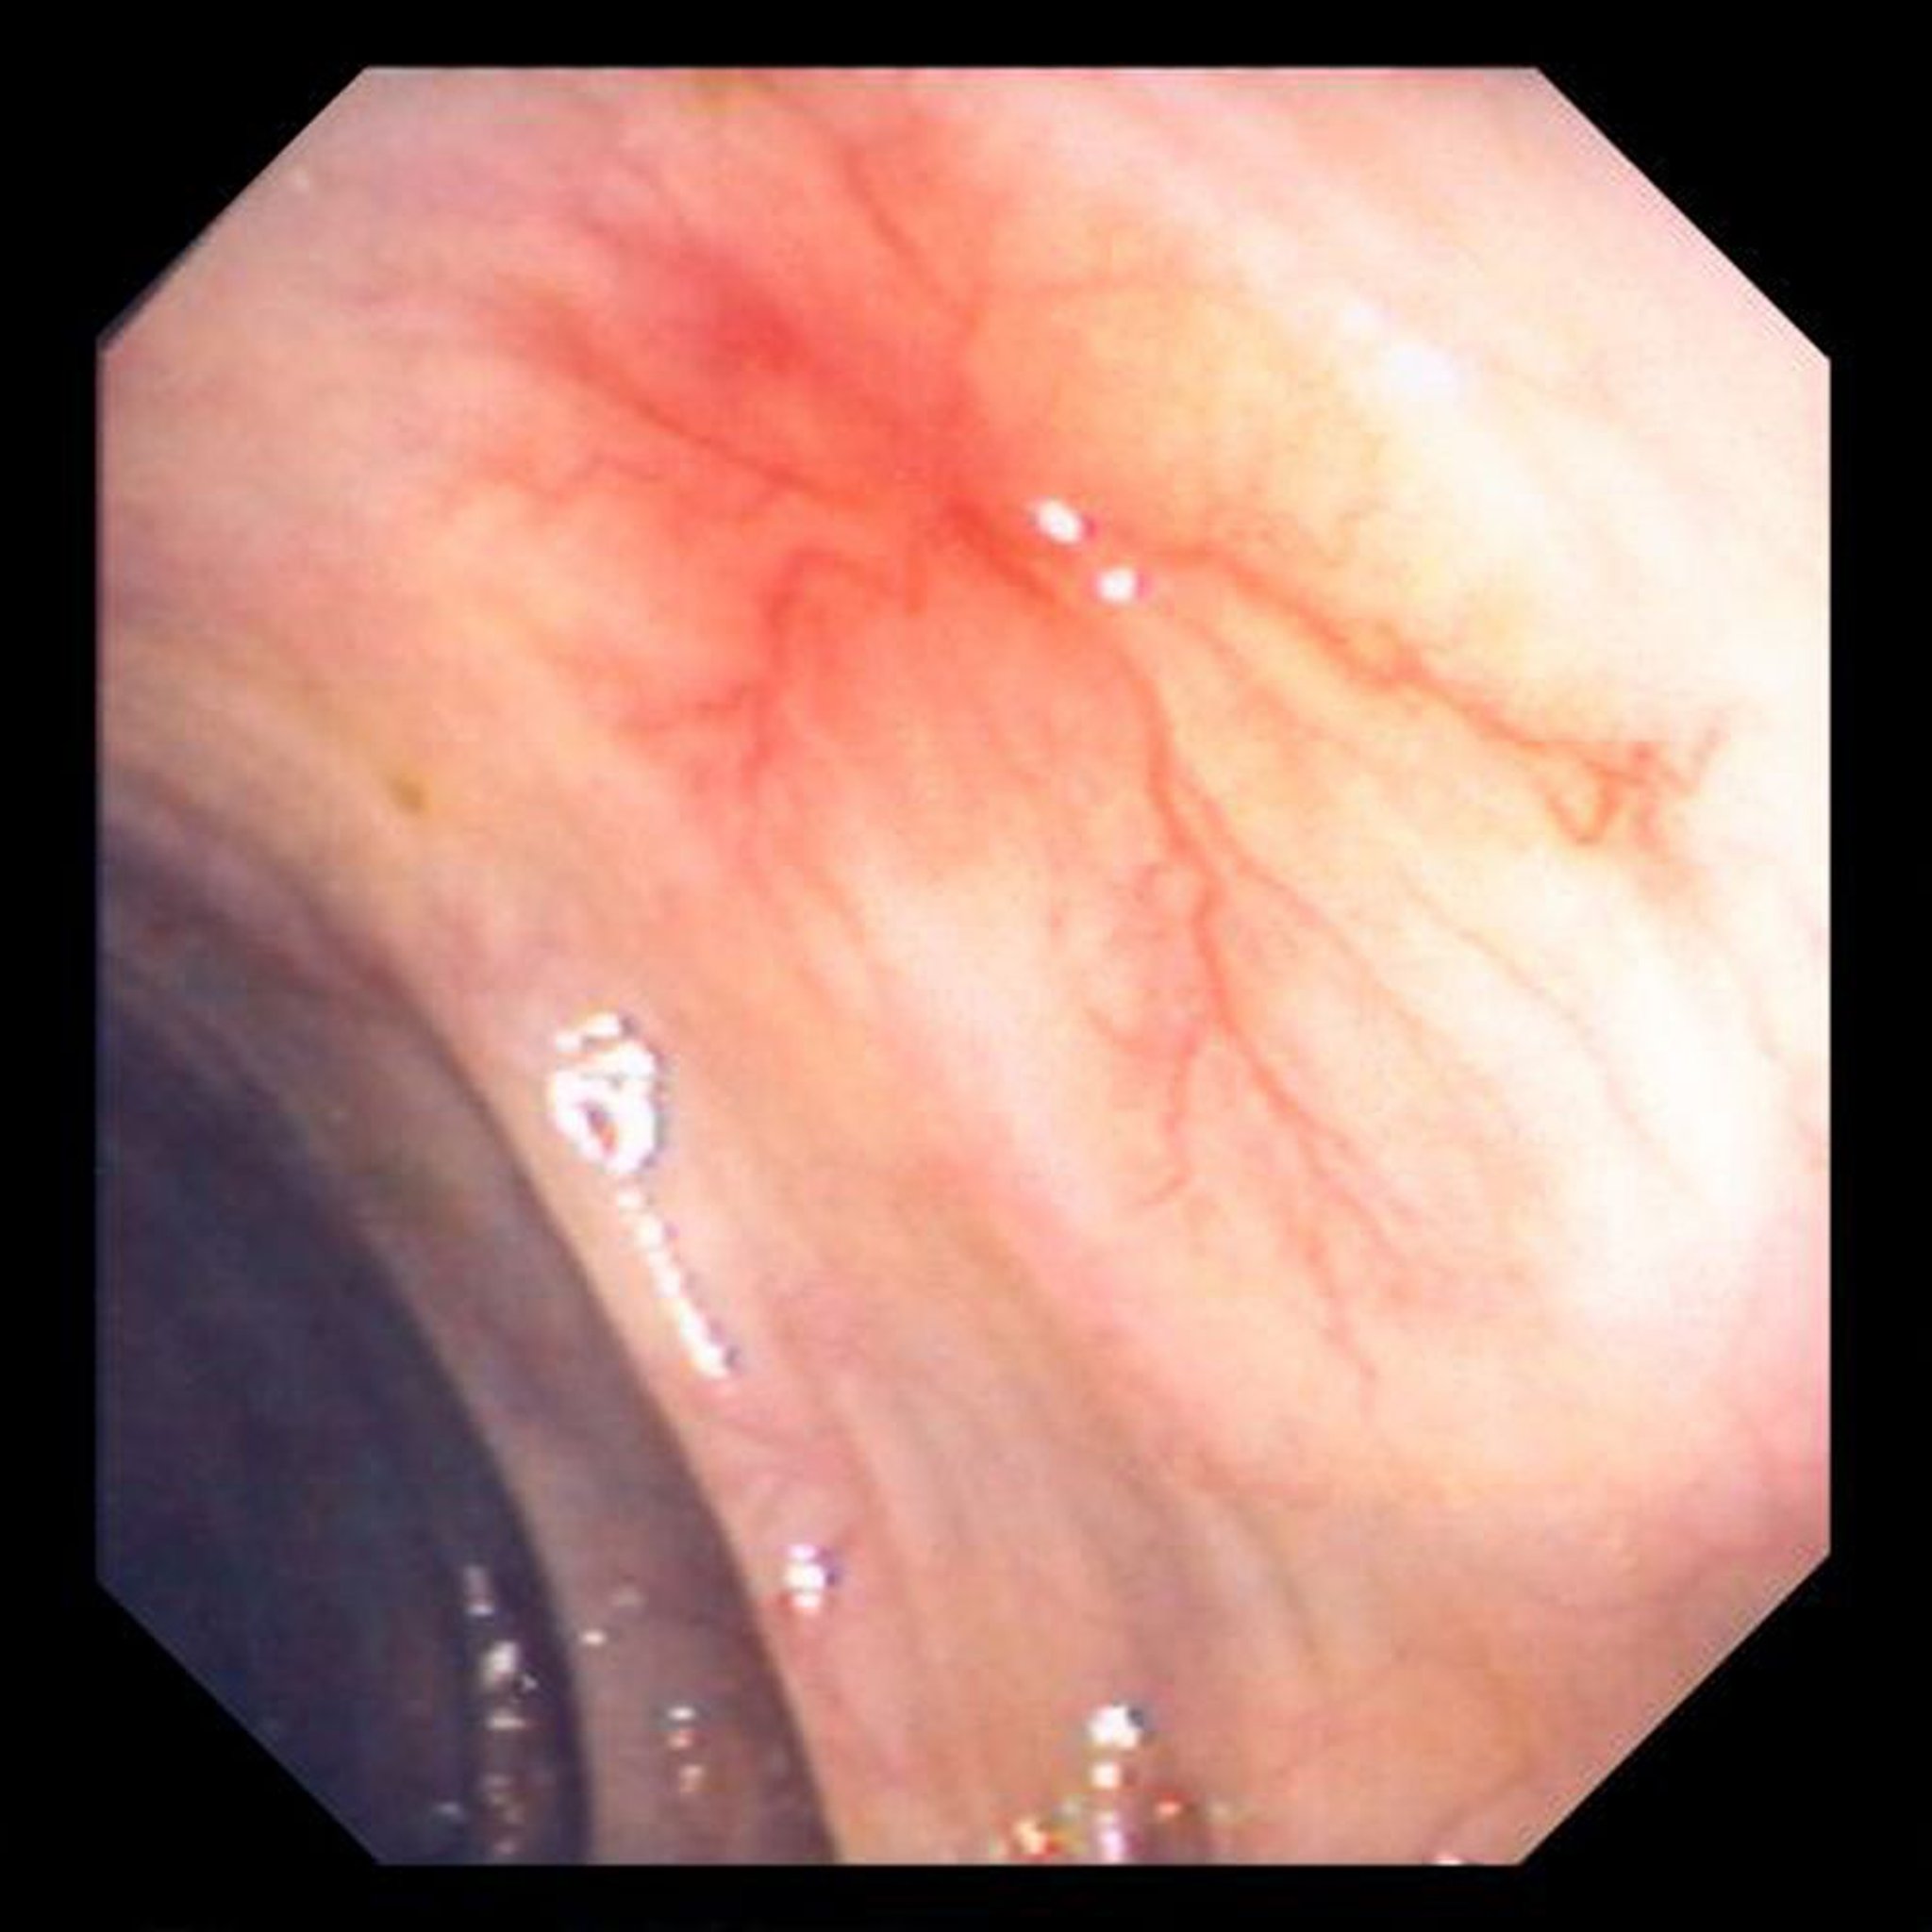

आंत में असामान्य रक्त वाहिकाएं (एंजियोडिस्प्लेसिया)

यह तस्वीर पेट की दीवार में असामान्य रक्त वाहिका को दिखाती है।

छवि डेविड एम. मार्टिन, MD द्वारा प्रदान की गई है।